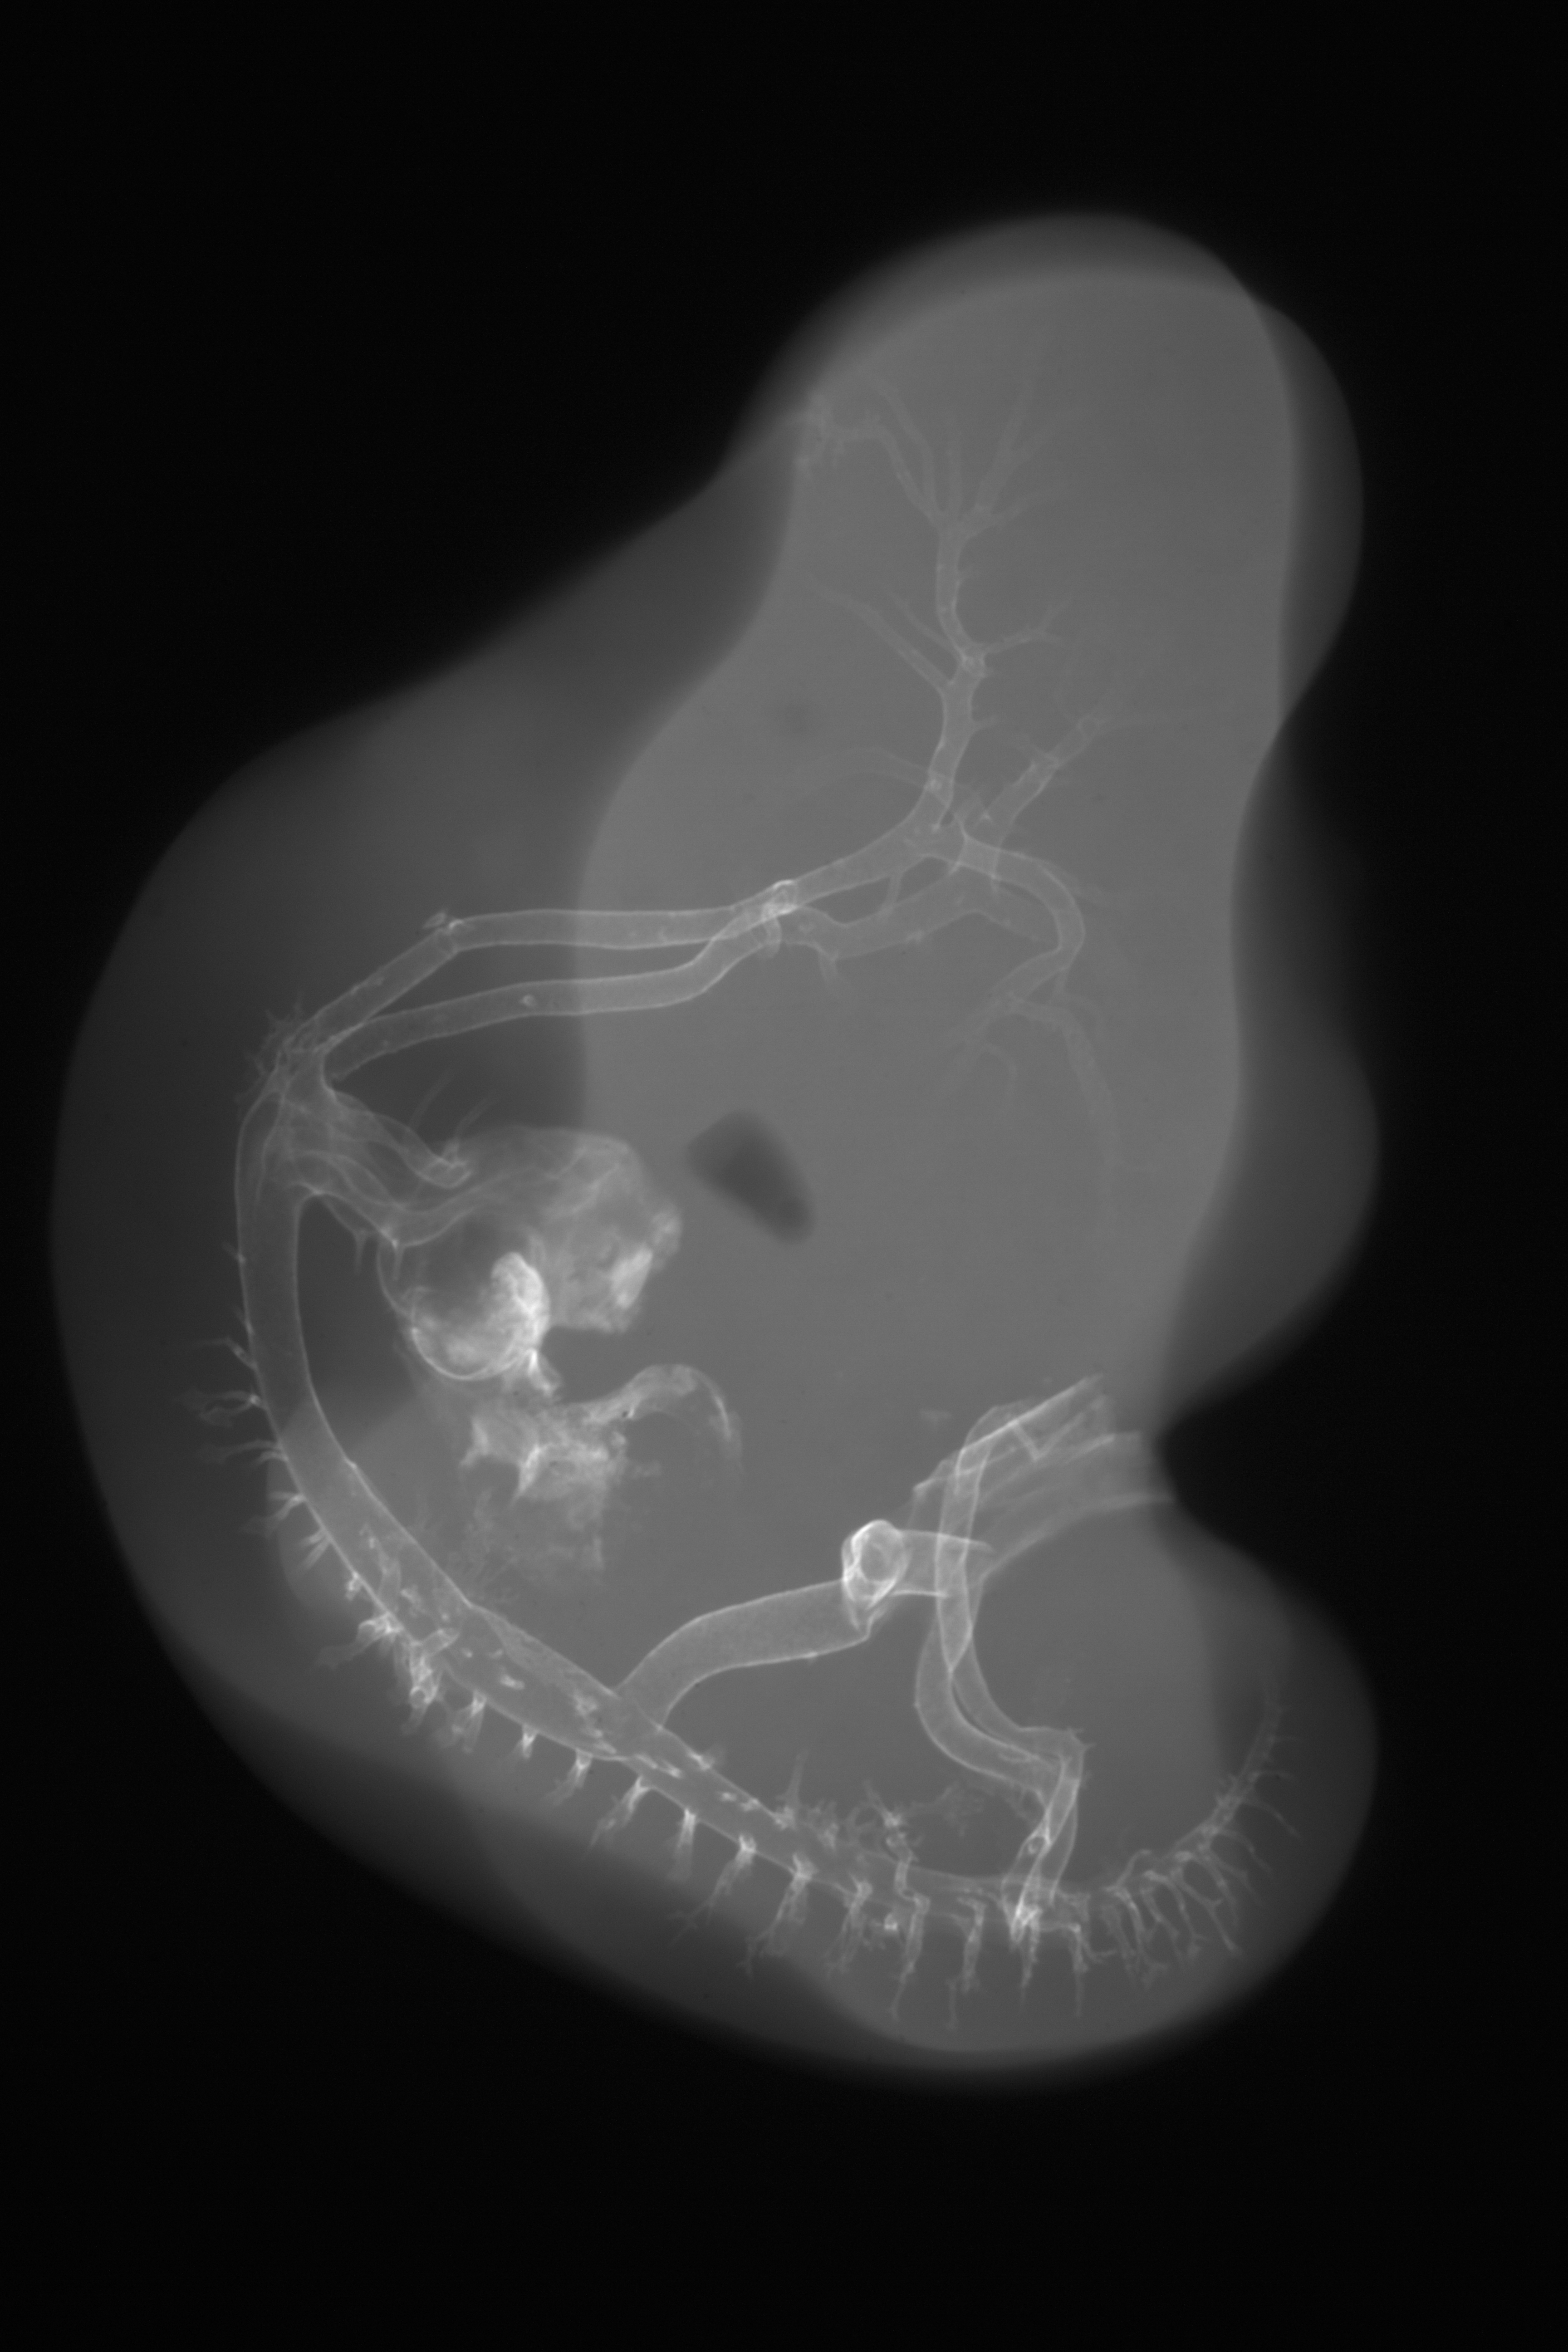

Chick Embryo Microangiography

Hamburger-Hamilton (HH) Stage 26 (approx. 5 days)

X-Ray Micrographs